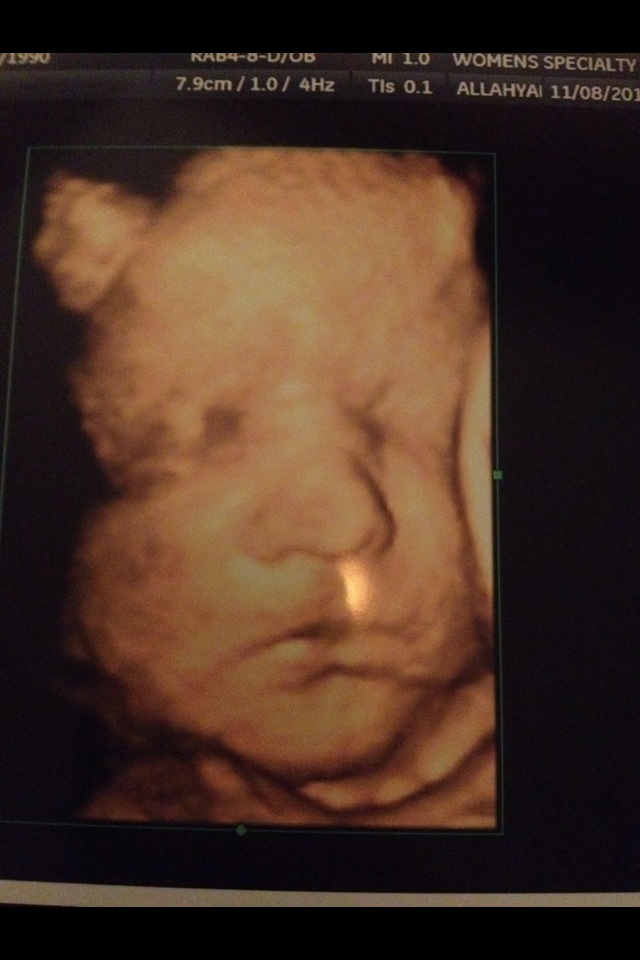

A little bit but not really. Here is baby A for a comparison he was born 6 days after this u/s I think it was so pretty close. And that's him a few hours after birth